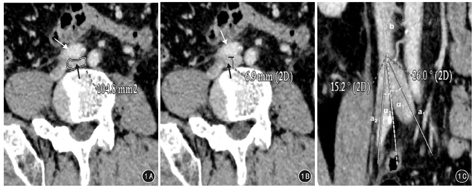

于正交断面髂静脉最大压迫部位处测量:短径指髂静脉受压最窄处管腔前后径;面积指髂静脉受压最窄处管腔面积;近远端髂静脉面积指受压髂静脉上下1 cm处未受压髂静脉的管腔面积(图1A);压迫范围指于垂直于髂动脉长径断面测量髂动脉压迫髂静脉最大压迫部位的短径(图1B)。

在平行于下腔静脉长径所建冠状面上测量夹角(α),要求显示下腔静脉和两侧髂总静脉及其汇合处(图1C)。